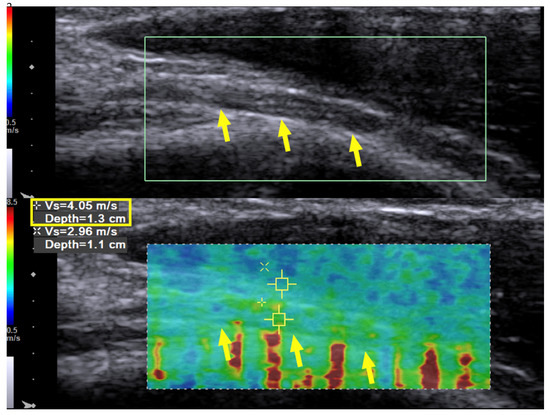

Case 1: A 31-year-old man sustained a left humeral shaft fracture in a traffic accident and underwent fixation with a dynamic compression plate. Fourteen months later, the plate was removed, after which the patient developed a wrist drop of his left hand. Neurodiagnostic studies (i.e., nerve conduction velocity and electromyography) were performed two months after the surgery and showed severe axonal damage with no signals from the radial nerve. Spontaneous activity was noted over the supinator, extensor carpi radialis longus (ECRL), extensor digitorum communis (EDC), and extensor indicis proprius (EIP) muscles, without any motor unit action potentials (MUAP) during recruitment. The ultrasound (US) examination showed a continuous radial nerve with an increased CSA and hypoechoic changes to the nerve fascicles at both the entrance to the spiral groove and supinator levels. Our US system (Acuson S3000, Siemens Healthcare (Pty) Ltd., Erlangen, Germany) entails a linear-array transducer with a bandwidth of 4–9 MHz. The SWV of the radial nerve was assessed using dedicated software (Virtual Touch Tissue Imaging Quantification (VTIQ), Siemens Healthcare (Pty) Ltd., Erlangen, Germany). With the VTIQ software, SWV can be assessed from 0–10 m/s. Segment-by-segment SWE was performed over the course of the radial nerve in the left upper arm, and increased hardness (SWV = 9.94 m/s) was identified at the entrance to the spiral groove, where the nerve starts to wrap around the humerus (Figure 1). The SWV of the contralateral side was 4.05 m/s (Figure 2).

Figure 2. Case 1: Ultrasound imaging with shear wave elastography. Long-axis ultrasound imaging of the radial nerve on the contralateral arm with shear wave elastography. Shear wave velocity measurement of the normal radial nerve was 4.05 m/s (longitudinal view at the beginning of the spiral groove). Yellow arrow and box: radial nerve in longitudinal view.